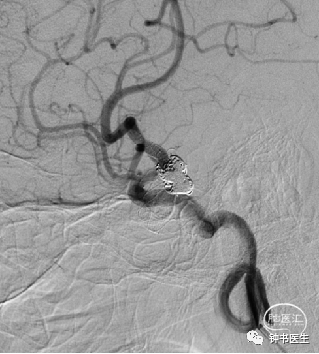

2021-07-05 DSA

Tubridge 4045

TB植入后动脉瘤即刻不显影。